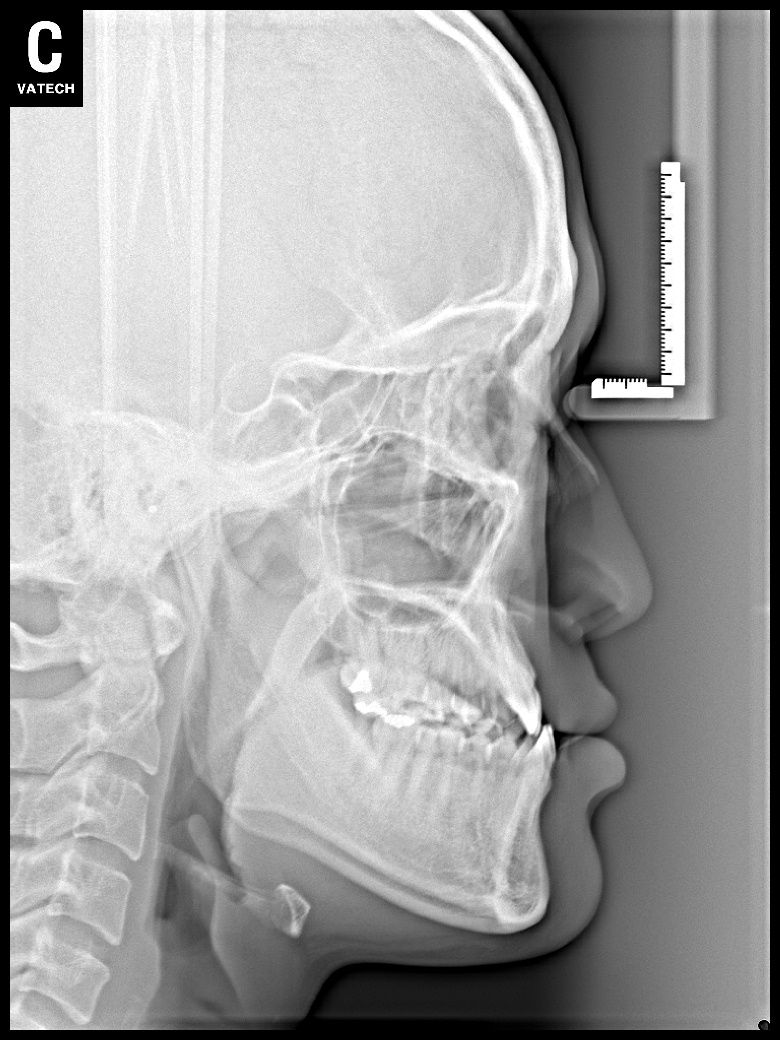

치료 전 사진입니다.